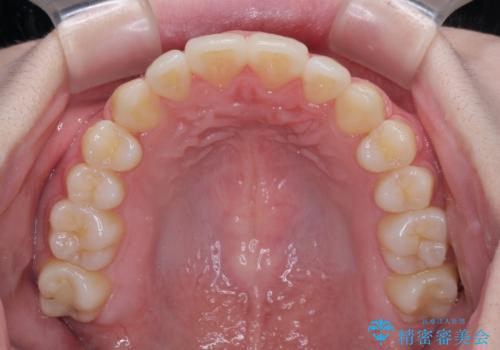

カリエール・ディスタライザーとインビザラインを用いた八重歯の改善

- 前歯の叢生と上顎左右の八重歯を気にして来院された患者様です。

奥歯の咬み合わせを見ると、左側は上顎が下顎に対して相対的に前方にあり、上下の前歯が接触していない状態でした。

咬み合わせを改善するためには、左側上顎臼歯を後方に移動させた咬み合わせにする必要があります。

インビザライン単体で改善することも可能性もありますが、インビザライン単体で達成する可能性が低いと考えられたため、カリエール・ディスタライザーという補助装置を併用して、より確実性を上げることとしました。

奥歯の咬み合わせを改善しながら、並行してインビザラインで歯列を整えることとしました。

カリエールディスタライザーを併用したことで、左側臼歯の咬み合わせを確実に改善させることができました。